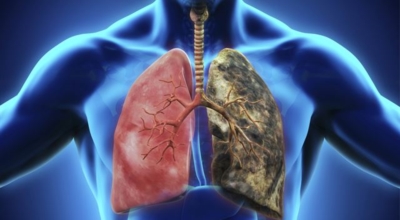

5. 긴 시간의 흡연은 기도의 보호 메커니즘을 훼손시켜 기관, 기관지, 폐 간질 및 폐에 훼손을 주어 폐 기능의 건강에 영향을 미쳐요.

인체가 순조롭게 기능을 발휘하려면 폐 건강이 필수다. 폐는 인체가 효율적으로 움직이는 데 있어 바퀴 안에 있는 톱니 같은 역할을 하기 때문이예요. 산소를 제공하는 폐 기능이 감소하게되면 폐렴이나, 만성 폐쇄성 폐질환(COPD), 천식 등 정도가 심한 호흡기 질환 발생 위험이 증가해요. 이런 질병들은 폐를 공격해 숨쉬기 힘들게 만들어요.

특별히 현대 사회에서 폐는 가장 시달리는 장기 중 한 종류다. 가지가지 공해 성분으로 오염된 공기에 미세 먼지, 황사까지 더하면 폐 안쪽에 있는 허파꽈리(폐포)부터 정도가 심한 훼손을 입습니다. 따라서 폐 건강을 증진시키기 위하여는 폐에 좋은 음식을 섭취할 필요가 있어요.